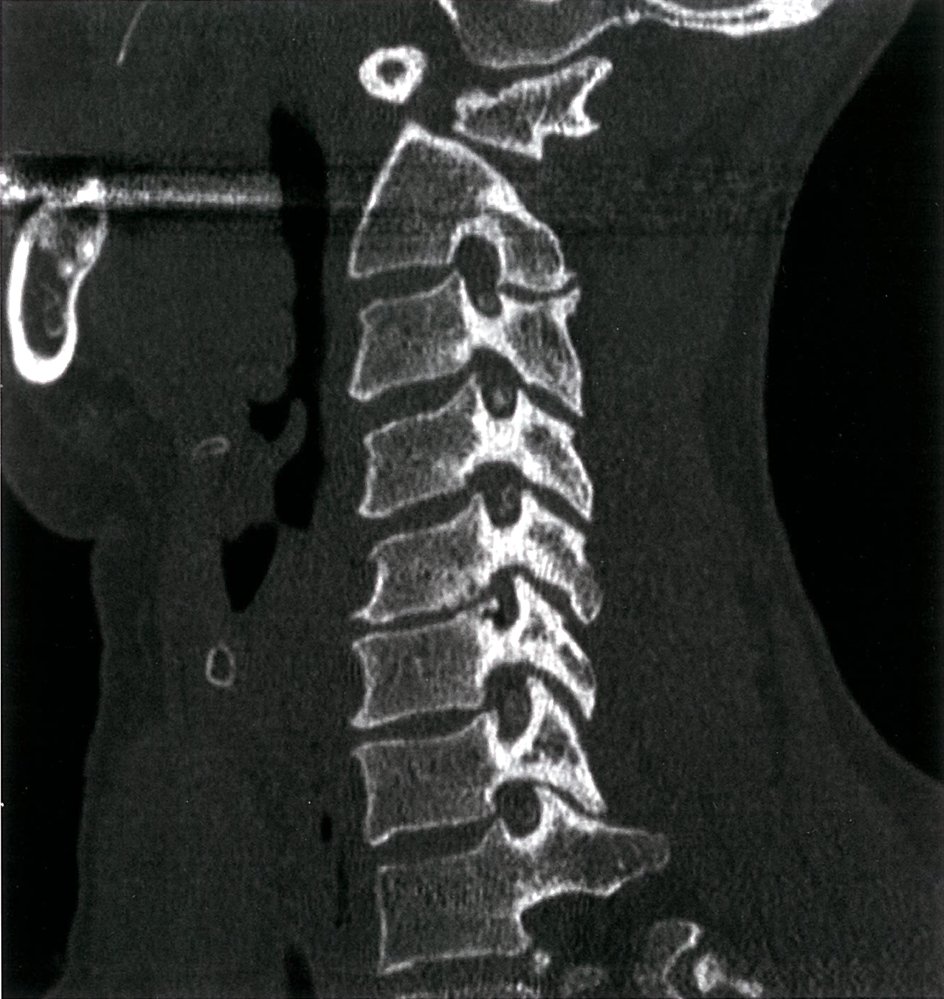

• Cervical x-ray : initial imaging test

• Reduced diameter of the spinal canal

• Degenerative changes of vertebral joints

• Osteophyte formation

• Narrowing of the disk space

• MRI of the spine (imaging modality of choice) : determines the site of narrowing of the medulla and the underlying pathology

• Myelography (possibly with CT): if MRI is contraindicated (e.g., in patients with metal implants)